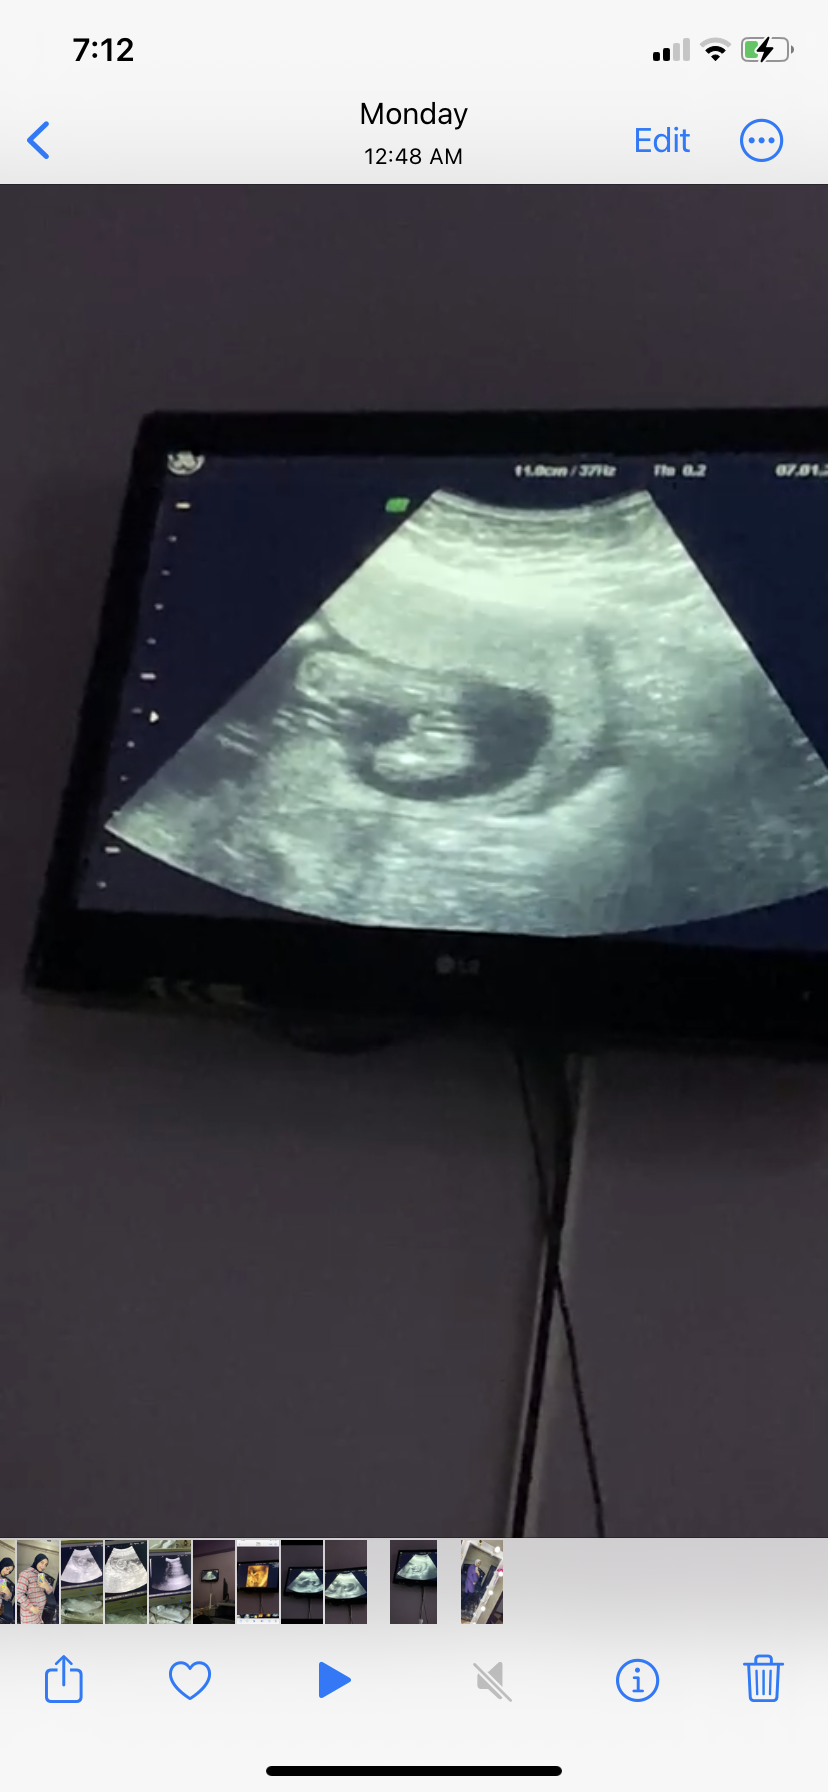

هل جنس المولود واضح من الصوره ولا ده حبل سري

هل يظهر جنس الجنين بشكل واضح في الاسبوع الثاني عشر ام ان هذا الحبل السري هل الجنين ذكر ام انثى...

هل جنين ذكر ام هذا الحبل السري

انا حامل بالاسبوع 13 ويوم1 . هل جنس المولود يبان الحين